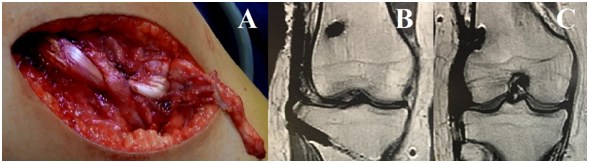

Knee radiographs revealed the Segond fracture (Figure 1A & 1B). The patient underwent an MRI and a computed tomography (CT). Both CT and MRI showed the Segond fracture. The MRI showed integrity of the ACL, posterior cruciate ligament (PCL), medial collateral ligament (MCL), posterolateral corner (PLC) structures and menisci (Figure 2A-2E).

Figure 1 A: Anteroposterior radiography demonstrating the Segond fracture. B: Lateral radiograph

Figure 2 A: CT with 3D reconstruction demonstrating the Segond fracture; B: Sagittal MRI showing an intact ACL; C: Ccoronal MRI showing the Segond fracture; D: Coronal MRI showing an intact MCL; E: Coronal MRI showing an intact posterolateral corner; F: Arthroscopic view showing an intact ACL.